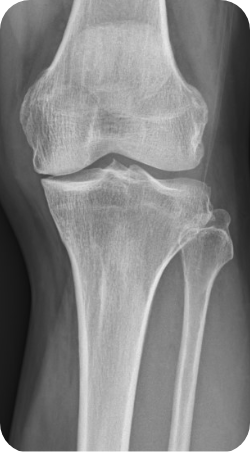

무릎 내측 관절면의 관절염이 심한 경우 관절 간격이 좁아지게 되면서 다리가 O 자형으로 변하게 됩니다. 이런 상태를 방치하게 되면 무릎 내측에 실리는 체중 부하가 늘어나면서 관절 간격이 더 좁아지게 되는 악순환이 이어지게 되는데, 이런 경우 다리의 모양을 1자형 혹은 X자형으로 만들어 무릎 관절 내측에 실리는 체중 부하를 줄이고, 관절염의 진행을 막을 수 있는 수술 방법이 근위경골 교정 절골술 입니다.

- 65세 이하 무릎 내측에 국한된 관절염

- O 다리, X 다리 등 휜 다리인 경우